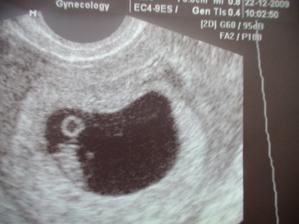

15.12.2009 Utz 6tt+3... miláček měří CRL 0,5cm a srdíčko na nás bliká🙂 Mamince je celý den šoufl🙂 ale má velikou radost🙂

22.12.2009 KO utz 7tt+3. Kontrola proběhla v pořádku máme CRL 1cm🙂 srdíčko krásně tluče.